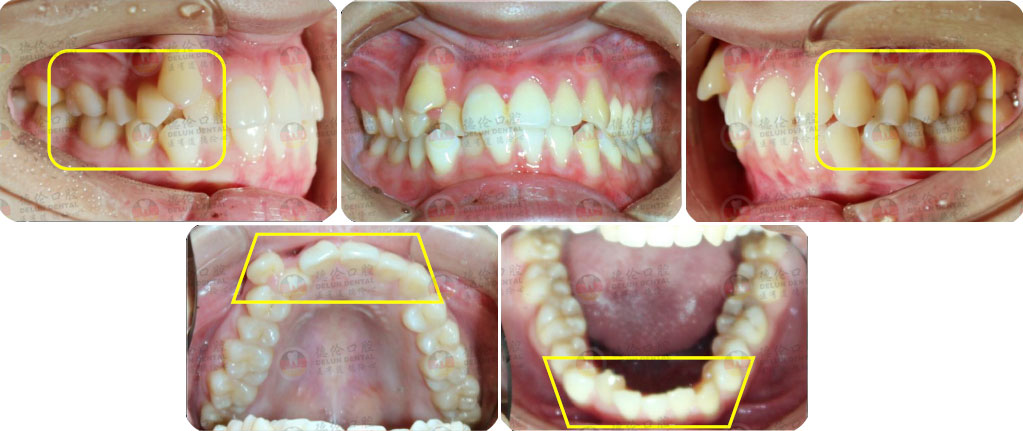

- 【診斷】

骨性I類,均角,安氏I類

上牙列重度擁擠,下牙列輕-中度擁擠

上中線右偏

13唇側(cè)錯(cuò)位

- 【治療方案】

拔除14,排齊上牙列

下頜尖牙適當(dāng)擴(kuò)弓,配合適量鄰面去釉,排齊下牙列

上頜左側(cè)配合適量鄰面去釉,調(diào)整中線

盡量調(diào)整后牙為尖窩咬合關(guān)系

矯治前后對(duì)比

蛻變周期:上頜16個(gè)月,矯治效率提升30%,下頜12個(gè)月,矯治效率提升20%

矯

治

前

口

內(nèi)

照

后